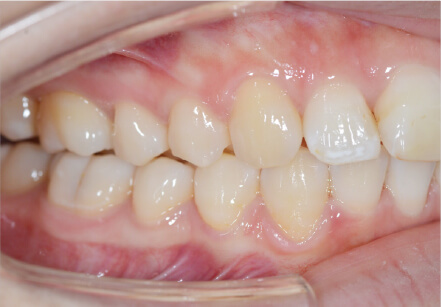

叢生の症例

10歳

/

女性

相談内容

スペース不足

カウンセリング・診断結果

myoからの移行。スペース不足のためインビザライン開始。

治療内容・方法

全額アライナー矯正

術後の経過・現在の様子

クリアライナー使用

治療のリスク

痛み・歯根吸収・歯肉退縮・虫歯・後戻り

費用・治療期間

(インビザのみ)385,000円、1年2ヶ月 + myo3年4ヶ月